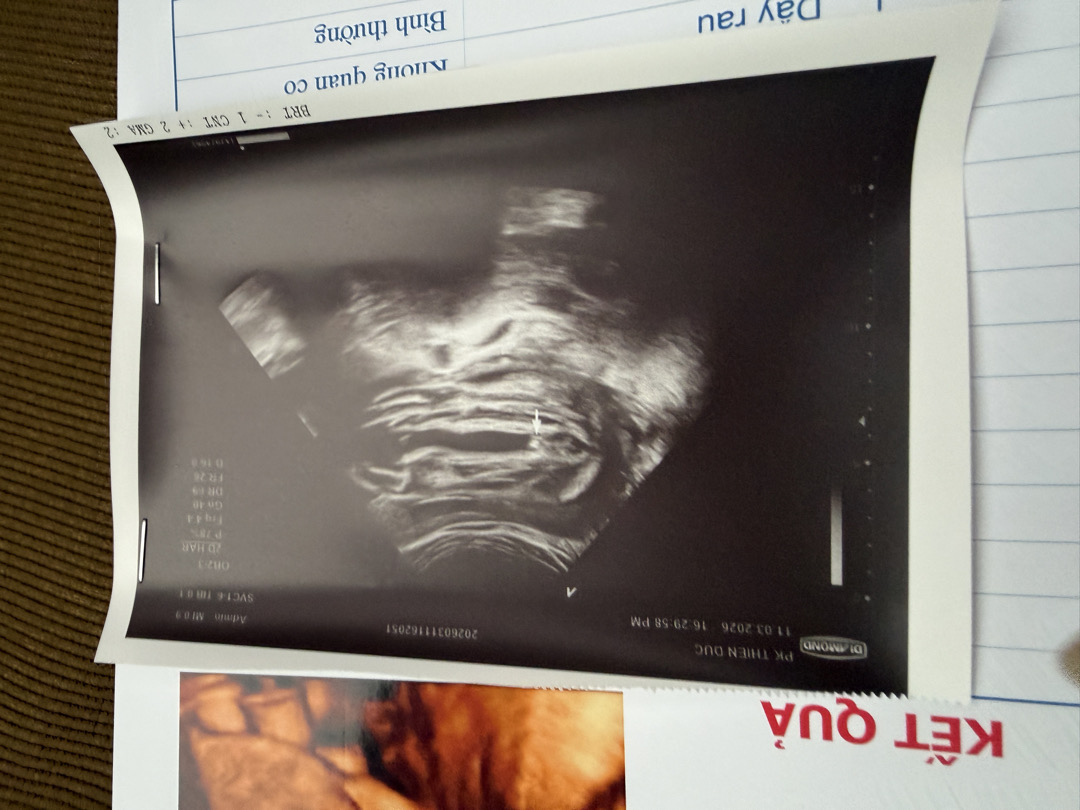

Hình ảnh siêu âm bé trai 17 tuần

Hình ảnh siêu âm bé trai 17 tuần cho mẹ thấy được điều gì?

Bộ phận sinh dục của bé trai được đặc trưng bởi bìu và dương vật nên dễ quan sát hơn bộ phận sinh dục của bé gái. Bộ phận sinh dục của bé trai thường có dạng một vệt sáng trắng lớn, do cấu trúc mô sụn của dương vật.

17w Mình đi siêu âm bác sĩ cũng chỉ vào đó rồi nói nè bé trai nhá, sướng nhá. Kk

Thường là thời điểm này xác định giới tính đúng rồi